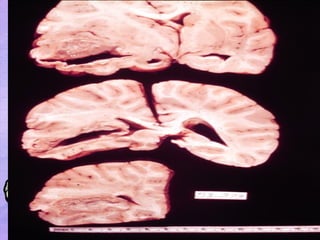

FEW PICTURES RELATED TO BRAIN ABSCESS

FEW PICTURES RELATEDTO BRAIN ABSCESS